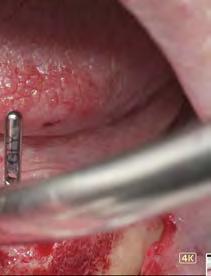

–Corticotomías y Ortodoncia. Ampliando límites del movimiento dental, por la Dra. Aranzazu Senosiain y cols. [50]